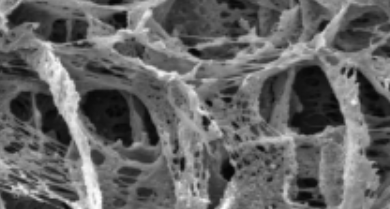

Intervertebral disk degeneration remains one of the most challenging health problems. In the current study, allopurinol was loaded into the chitosan nanoparticles and then incorporated into chitosan/alginate hydrogels and then further studied for its disk regeneration potential in a rat model. In vitro studies were performed to characterize the hydrogel system, including scanning electron microscopy, cell viability assay, cytoprotection assay, cell migration assay, swelling assay, and drug release assay. In vivo study was performed in a rat model of the intervertebral disk injury. Animal studies showed that allopurinol-loaded hydrogels had significantly higher disk regeneration potential compared with other experimental groups. The gene expression studies showed that the animals treated with allopurinol–loaded hydrogel had significantly higher tissue expression levels of type I and type II collagen genes than other groups. Furthermore, the tissue expression levels of nuclear factor κB (NF-κB) and glutathione peroxidase (GPx) genes were significantly lower in this group. The relative expression levels of type I collagen, type II collagen, NF-κB, and GPx genes in the allopurinol-loaded hydrogel group were 2.77 ± 0.2%, 2.86 ± 0.25%, 0.58 ± 0.03%, and 0.45 ± 0.02%, respectively. We showed for the first time that allopurinol-loaded hydrogel promoted intervertebral disk repair, which could be due to its potential to modulate oxidative stress, reduce inflammation, and improve matrix synthesis.